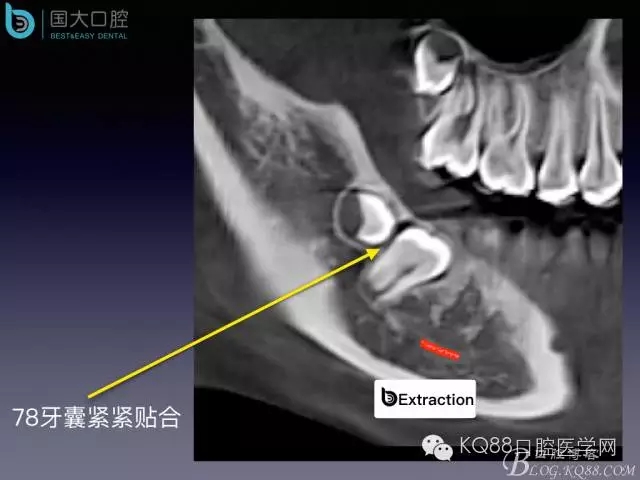

阻生牙的預(yù)防性拔除

- 牙齒拔除適應(yīng)證及第二磨牙遠中齲病